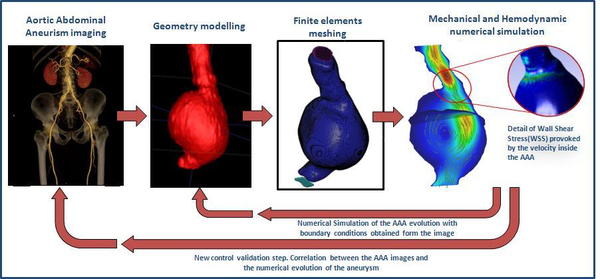

(1.13) |

When we have a large Reynolds number inertial forces are dominant over viscous forces and viceversa. This naturally leads us to the role of Reynolds number as the key parameter which identifies the transition of the flow to turbulence. Usually, Reynolds number suggests that in most arteries of the cardiovascular system the flow is laminar. The exceptions are the flow in severely stenotic vessels, where the flow regime can be become transitional or turbulent. Turbulence blood flow implies fluctuating pressure acting on the arterial wall, and fluctuating, increased shear stress, which can be provoke post-stenotic dilation or atherogenesis. In this monograph, blood flow has being considering laminar. Figure 9 shows the full process from the medical image to the numerical simulation: aortic abdominal aneurism imaging, geometry modelling, finite elements meshing and mechanical and hemodynamics numerical simulation.

|

| Figure 9: From the medical image to the simulation |